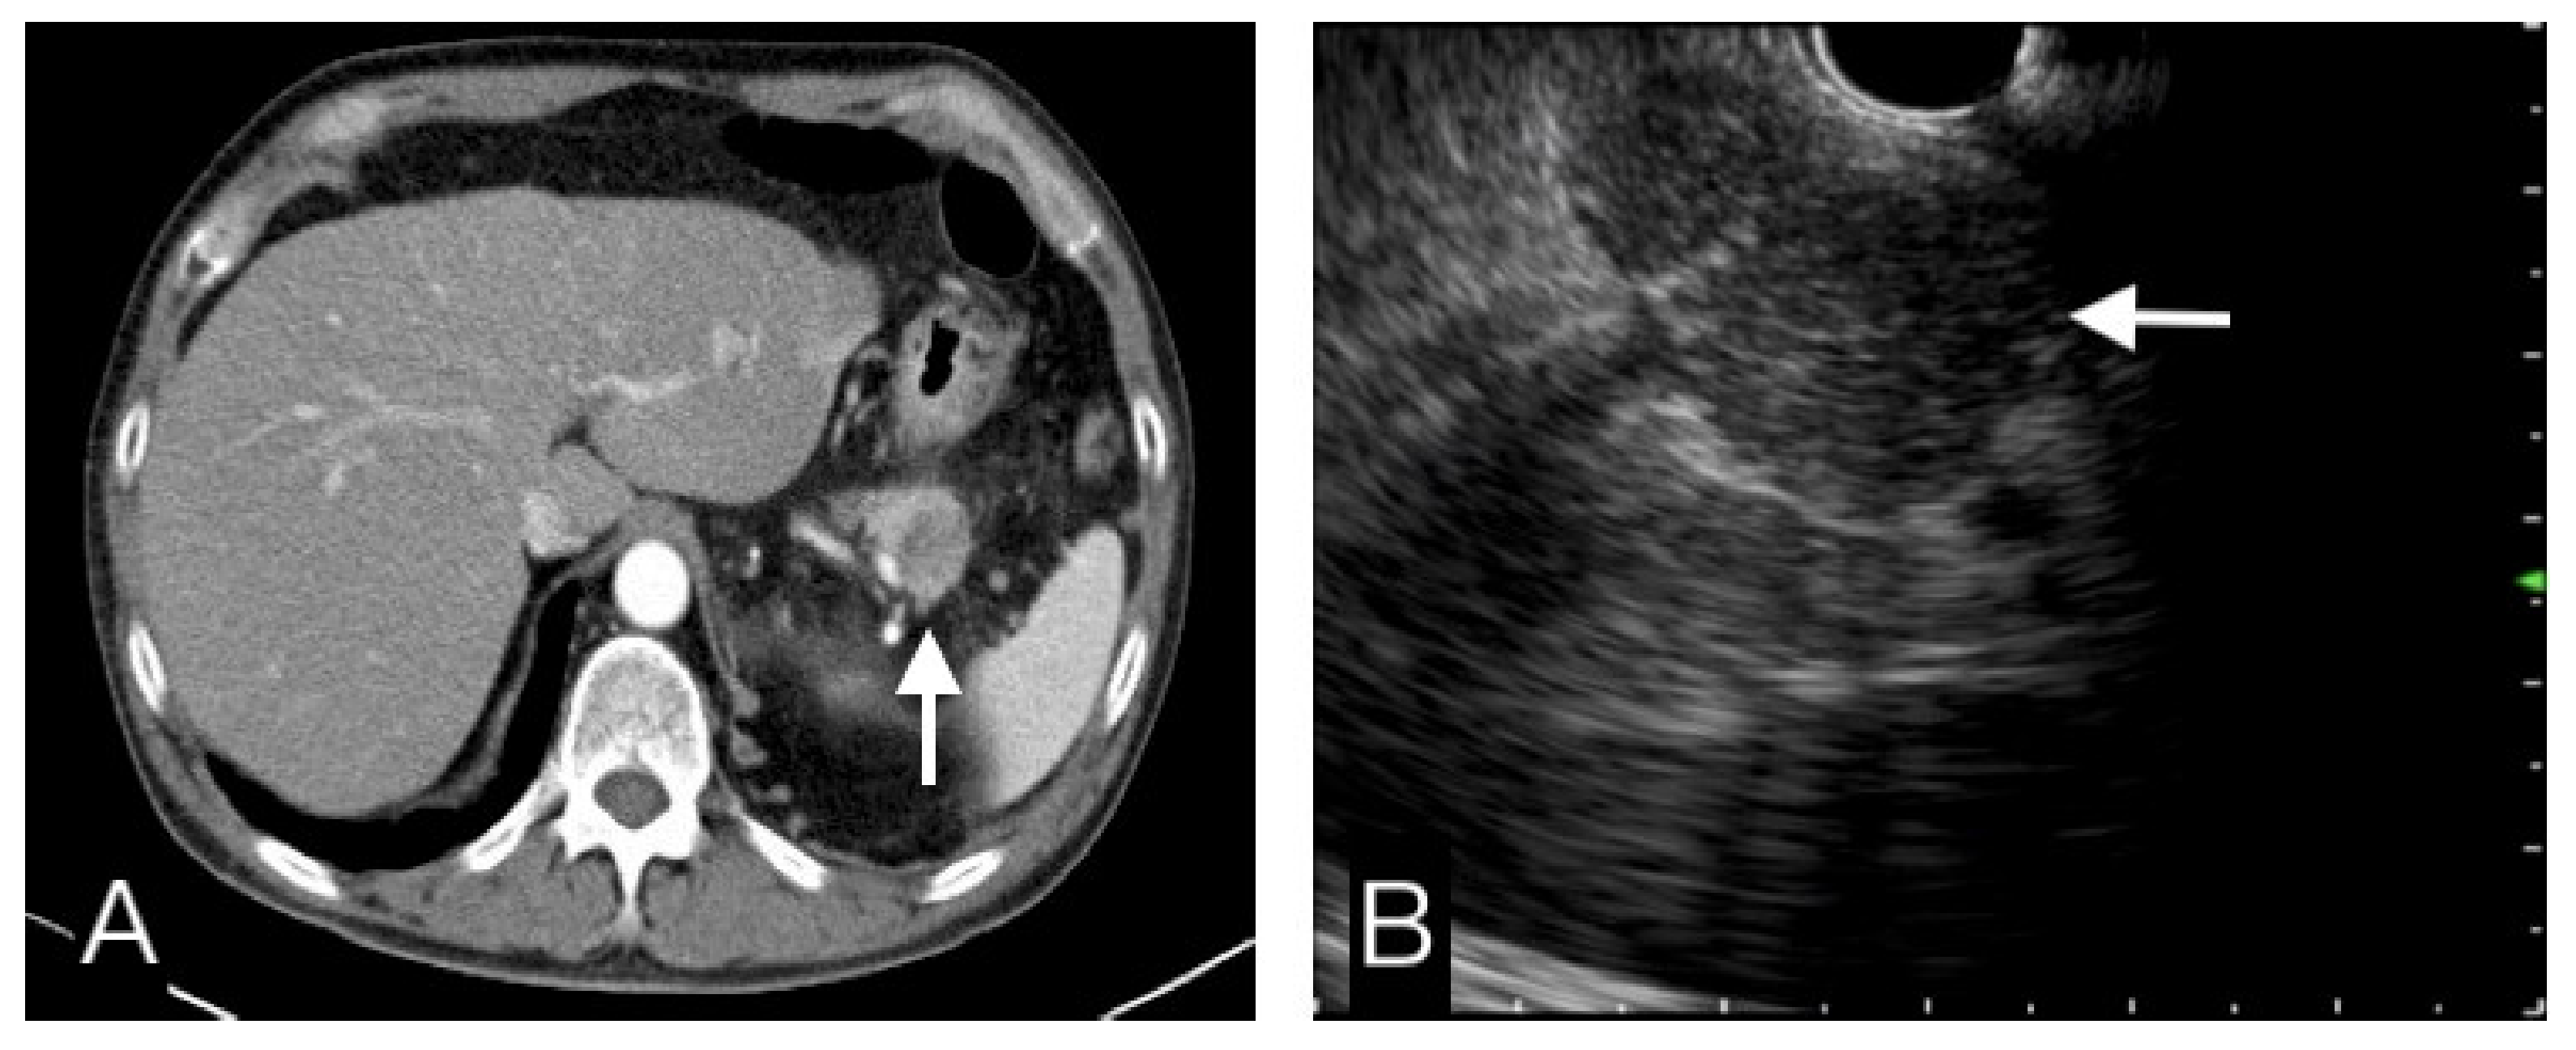

Figure 4.

This pancreatic tail tumor had a hypo-attenuating pattern in CT (A), and an iso-echoic pattern in EUS (B). Benign etiology was more favor diagnosis than malignancy. FNB cytopathological results, clinical and image follow-up confirmed this was a benign tumor.